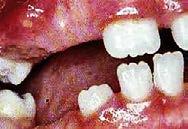

Síndrome de Down. El cual entre sus características a nivel bucal, presenta un subdesarrollo de los maxilares, mal posición dentaria, disfunción lingual, retraso en la erupción dentaria, ano malía de tamaño y forma dentaria, cambio en las características cuspí deas, dientes cónicos o concavidades en la superficie labial (Figura 16-18).

También el síndrome de Treacher Collins, donde los pómulos, mandíbula y mentón son muy pequeños en pro porción a las demás estructuras facia les, además, las orejas con disarmonía en el contexto facial y la presencia de un orificio en el paladar (Figura 19).

Otro síndrome es el de Pierre Robin, el cual presenta algunas característi cas relevantes, que de igual manera influyen en un desarrollo complejo de la articulación, como la retrognacia y glosoptosis con o sin fisura palatina y obstrucción respiratoria (Figura 20).

Es entonces que podemos observar que el labio y paladar hendido (Hen didura orofacial) es una manifesta ción orofacial presente en más de 40 síndromes, no siendo un síndrome independiente como tal (Figura 21).